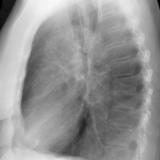

RLL Collapse  1 Lateral

Date: 02/28/2004

Views: 3257